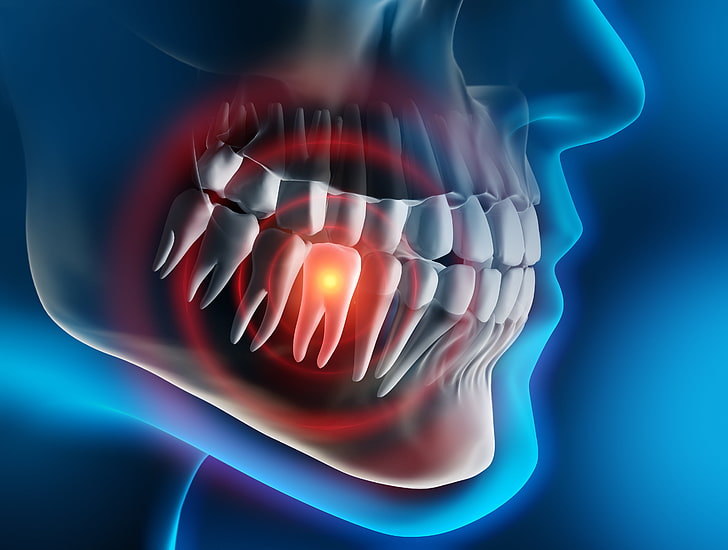

www.freepik.com3d Tooth Animation With Broken Teeth Background, 3d Illustration Sick

www.freepik.com3d Tooth Animation With Broken Teeth Background, 3d Illustration Sick

صورة لسن مكسور على خلفية سوداء, 3d التوضيح الأسنان المريضة يشعر ويقلق

pixabay.comPremium AI Image | 3D Broken Teeth Cracked Teeth Tooth Fractures Mouth

pixabay.comPremium AI Image | 3D Broken Teeth Cracked Teeth Tooth Fractures Mouth